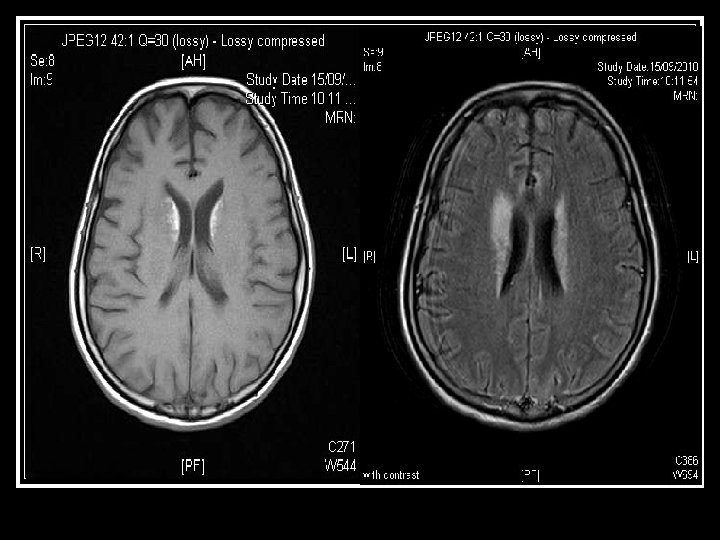

(4) Neurologist assessment: summary Initial presenting illness n Bulbar palsy with normal NCT, but clinically nil response to IVIG and steroid Deterioration right now n Cerebral dysfunction with raised CSF protein n Hypointensities in bilateral temporal and Rt BG Need to consider other diagnosis n Sinusitis with orbital + CNS extension n For contrast MRI brain + skull base

Searching for an answer, again…. . n n n n n 9 th July: Plain CT Brain (Hospital A) 7 th Aug: Plain CT Brain (Hospital A) 25 th August: Plain CT Orbit (Hospital A) 27 th August: Contrast CT brain + Sinus 4 th September: MRI brain + brainstem 4 th September: Plain CT brain 10 th September: Contrast CT brain 11 th September: Plain CT sinus 15 th September: MRI brain + DWI

Brain was so ill, but no answer…. Condition since 4 th September 2010 n Multi-focal inflammatory change over bilateral basal ganglia/ thalamus/ temporal lobes and brainstem on MRI, unlikely due to bacterial infection n GCS E 4 Vt. M 1 and all limbs flaccid n Persistent high fever and tachycardia despite Vanco/netro/fluconazole 14 days

Summary of progression • June/ 2010 n • July/ 2010 n • Early Aug/ 2010 n • Late Aug/ 2010 n • Sept/ 2010 n Lt face weak Bulbar palsy Dilated Rt pupil and uveitis Endophthalmitis and high fever Deep coma, tetraplegia, high fever n n n Nil imaging Facial neuritis Bilateral basal ganglia change Bilateral temporal + BG + thalami + pons